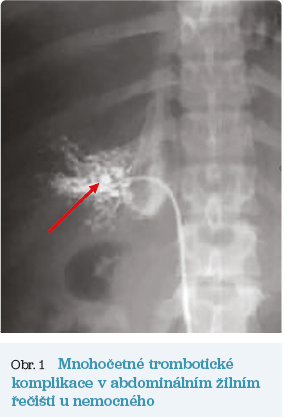

Obr. 1 Mnohočetné trombotické komplikaceV říjnu 2000 byl pacient vzhledem k věku odeslán k dalšímu sledování do Ústavu hematologie a krevní transfuze (ÚHKT) v Praze. Na kontrolu se však nedostavil. V lednu 2007 (ve věku 25 let) pozoroval opakované bolesti břicha spolu s progredujícím otokem břišní stěny a nárůstem hmotnosti. Při vyšetření hepatologem na interní klinice byl zjištěn ascites při Buddově–Chiariho syndromu (trombóza portální žíly a jaterních žil, parciální trombóza ilických žil a dolní duté žíly) – viz obrázek 1. Byly přítomny laboratorní a klinické známky jaterního selhávání, anémie a hyperkoagulačního stavu (tab. 2). Nemocný byl léčen diuretiky, nízkomolekulárním heparinem a byl mu zaveden transjugulární intrahepatální portosystémový shunt (TIPS) s následným významným poklesem portosystémového gradientu. V květnu 2007 byl pacient konečně odeslán do ÚHKT, kde byla diagnostikována PNH (CD59 kompletní deficit: 35 % erytrocytů, 85 % granulocytů, 80 % monocytů; CD55 kompletní deficit: 44 % erytrocytů, 90 % granulocytů, 88 % monocytů). Nemocný byl léčen antikoagulační léčbou nejprve kontinuálním podáváním heparinu a poté nízkomolekulárním heparinem (LMWH) s následným převedením na warfarin v dávce 7,5–10 mg denně a úpravami dle kontrol INR (mezinárodní normalizovaný poměr). U nemocného byla nadále přítomna anémie s potřebou 2 TU erytrocytů měsíčně. V prosinci 2011 bylo u nemocného zahájeno podávání ekulizumabu ve standardním dávkovacím schématu 4× 600 mg každý týden a dále 900 mg každé 2 týdny. Již po 12 týdnech léčby došlo ke zlepšení hodnot krevního obrazu, k poklesu hodnot laktátdehydrogenázy (LDH) a jaterních testů (tab. 1). Přetrvávající vysoká hodnota celkového bilirubinu je důsledkem prokázaného Gilbertova syndromu. Opakované vyšetření výpočetní tomografií (CT) prokázalo mírný ústup trombotických změn s částečnou rekanalizací portální žíly. V současné době se nemocný nachází v remisi choroby, bez potřeby transfuzí, se stabilizací hodnot jaterních testů a bez známek progrese trombózy, nadále dostává ekulizumab v udržovací dávce 900 mg 1× za 2 týdny a perorální antikoagulační léčbu (tab. 1).